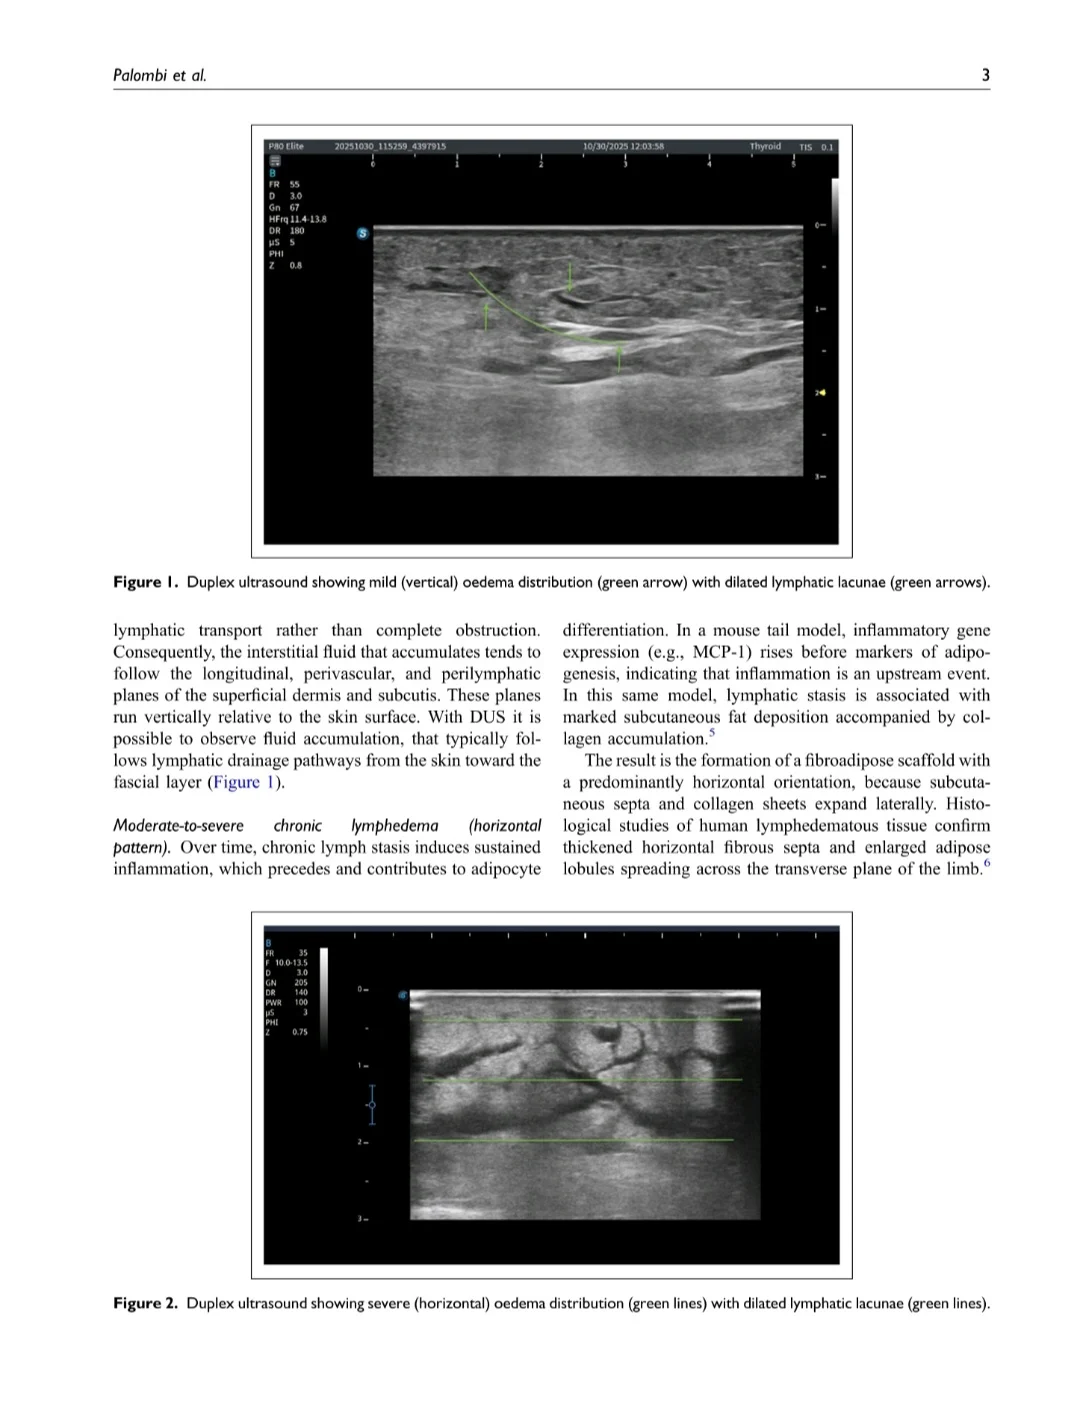

- Early/mild lymphedema tends to show a ‘vertical‘ pattern: fluid tracking from the dermis toward the superficial fascia along perivascular and peri-lymphatic planes

- Moderate–severe chronic lymphedema shows a ‘horizontal‘ pattern: transversely expanded, fibroadipose subcutaneous tissue with hypoechoic lymphatic lacunae